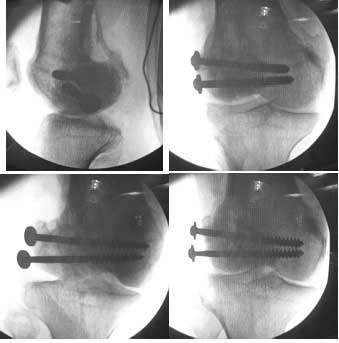

This was fixed temporarily, bone grafted with tricortical struts, and fixed by two cancellous screws. The fragment was not large enough to afford any fixation to a plate or such implant, and the screws held it compressed well to the rest of the distal femur.

Post-op - limb is well aligned, rom 0-30, but I am not pushing that right now, for the next two or three weeks.

Further plan - hope that the screws hold the fragment appropriately till union, but if the stability on table is anything to judge by, that should not be a problem.

Quadricepsplasty after a year or so, to restore flexion.

A good job, though personally I would have preferred the screws a bit longer.